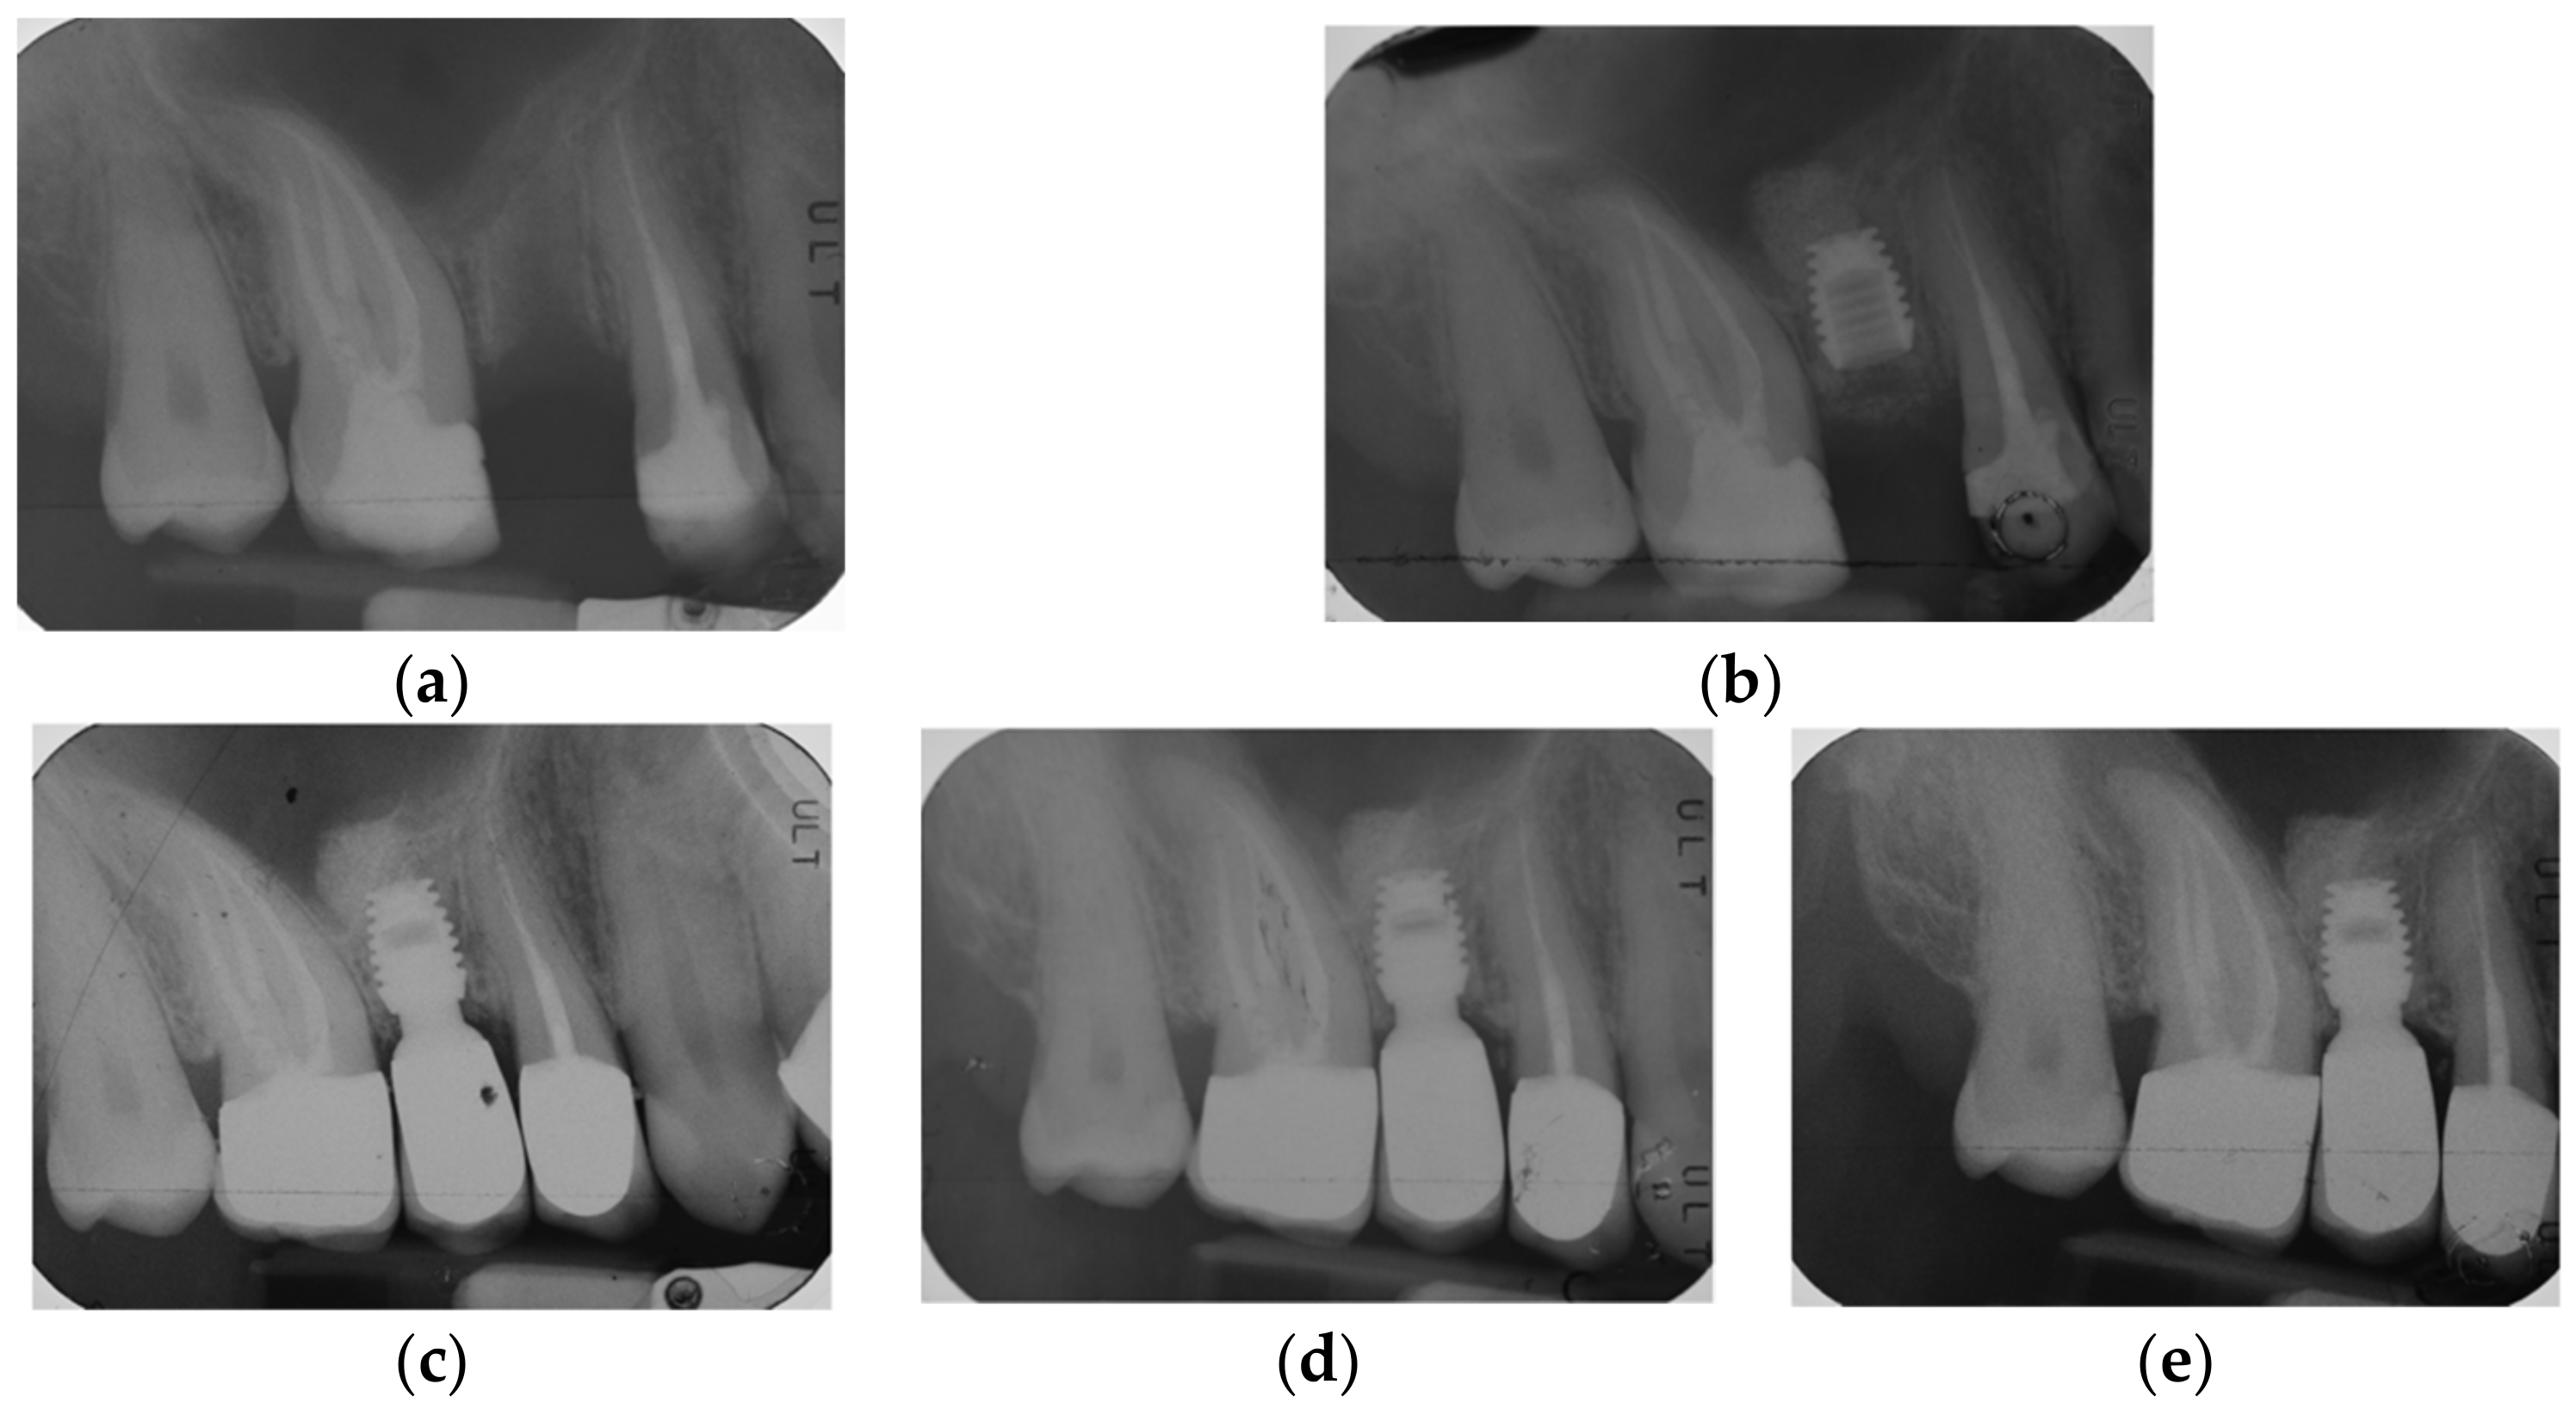

2.2. Surgical Protocol

2.3. Prosthetic Protocol and Follow-Up Evaluation

3.3. Radiographic Bone Levels

3.4. Patients’ Level of Satisfaction